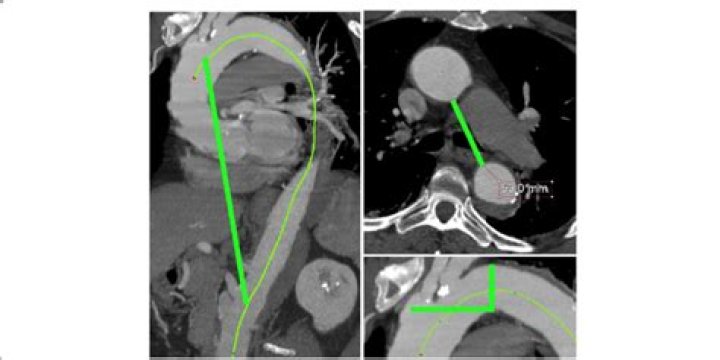

Tortuosity of the aorta was defined as the length of the midline within the aorta divided by the linear distance between the aortic root and the iliac bifurcation, and tortuosity of the ascending aorta was defined as the measured length of the ascending aorta divided by the linear distance between the aortic root and ...